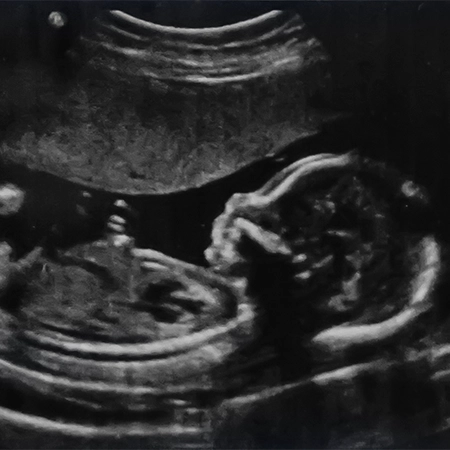

Image

Β' τρίμηνο